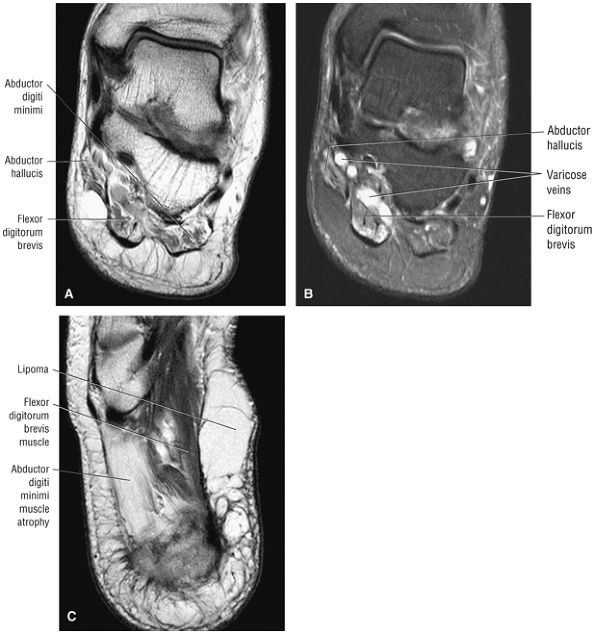

The first layer consists of the abductor hallucis, the flexor digitorum brevis, and the abductor digiti minimi (Fig. 5.75).

-